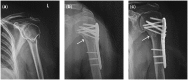

The current study is to observe the effect of the locking system strengthened by biomimetic mineralized collagen putty for the treatment of senile proximal humeral osteoporotic fractures. From January 2012 to December 2015, 80 cases of senile patients with osteoporotic proximal humeral fractures were randomly divided into an observation group and a control group, each group with a total of 40 cases. The control group was simply treated with locking plate. The observation group was treated with locking plate in combination with biomimetic mineralized collagen putty. The therapeutic effect thereby was observed. The excellent and satisfactory rate was 90% in observation group and was 72.5% in control group. The difference between the two groups was statistically significant (χ2 = 5.3312, P < 0.05). The fracture healing time was 11.82 ± 3.62 weeks in observation group and 19.78 ± 5.46 weeks in control group. The shoulder joint function score was 89.63 ± 8.12 in observation group and 76.92 ± 8.18 in control group. There was significant difference between the two groups (t = 7.1272; 12.7834, P < 0.05). The complication rate was 10% in the observation group and 32.5% in the control group (χ2 = 7.3786, P < 0.05). Locking system strengthened by biomimetic mineralized collagen putty has advantages such as accelerating healing of senile proximal humeral fracture, improving the therapeutic effect, reducing the complications. As one of the optimal internal fixation method, it provides a new option for better treatment of senile osteoporotic fracture.